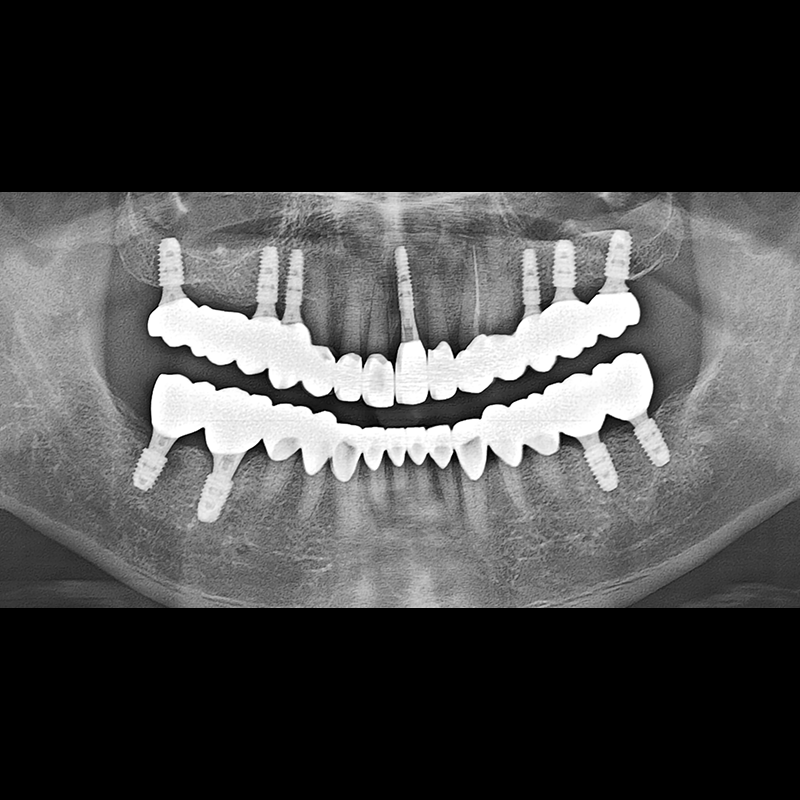

IMPLANT

BEFORE AFTER

임플란트 전후사진 2025.05.30

결손된 치아 부분과 살리기 힘든 치아 위치에 임플란트를 식립하였습니다.